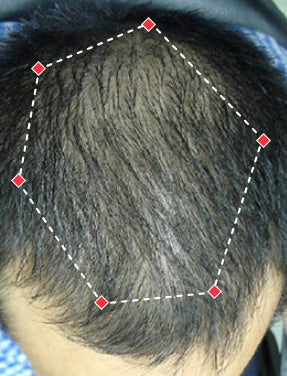

Indications for Use

The iRESTORE Hair Growth System Elite is indicated to promote hair growth in males who have Norwood-Hamilton Classifications of IIa to V and in females who have Ludwig-Savin Classifications I to II, and in both with Fitzpatrick Skin Phototypes I to IV. In other words, iRESTORE is not intended for people who are bald or have advanced hair loss.

Laser therapy works to reactivate thinning and dormant hairs. For completely bald areas of the scalp, there may be no way to promote hair regrowth. If you still have hair follicles, laser therapy may be beneficial to you.

Not sure? Email us to have our specialists evaluate your scalp conditions to see if iRESTORE is suitable for you.